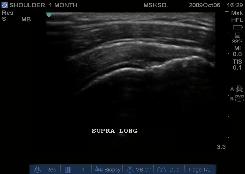

Case Study: Shoudler Pain for 1 month

Findings include Subluxing Bicep

Tendon, Inferior Margin Subscapularis

Tear.

CLICK IMAGE TO SEE MORE OF THIS

STUDY